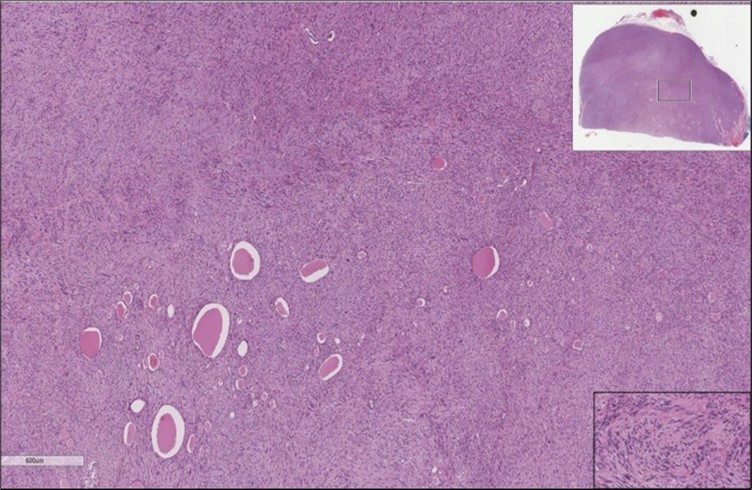

When diagnosing thyroid swelling, imaging studies have been helpful in differentiating malignant from benign tumors with US being used as an initial evaluation tool when assessing thyroid nodules. Tumors are categorized based on composition, echogenicity, shape, margin and echogenic foci into added scores determined by the TI-RADS system, which determines the need for FNA 13. Other imaging modalities include MRI and CT. However; radiological assessment does not distinguish between the types of thyroid cancer, and therefore FNA and biopsy are of crucial importance 3, 6. On a pathologic sample, LMS appears as spindled eosinophilic cells with elongated blunt-ended or cigar-like nuclei arranged in fascicles 2, 7 (Figure 1, Figure 2, Figure 3). Despite the unique microscopic morphology, LMS cannot be distinguished from other spindle cell tumors such as spindle cell variant of medullary thyroid cancer, anaplastic thyroid

Figure 1.Left thyroid Low power of the thyroid gland showing complete replacement of the thyroid by the neoplastic cells (H&E, ×4).

Figure 2.Left thyroid On a Higher power, few thyroid follicles are noted and the lesion is composed of spindle cells with sweeping fascicles (H&E, ×200).

Figure 3.Left thyroid The malignant looking cells are showing diffuse atypia, mitosis and hyper-chromatic nuclei, some remaining follicles could be noted as well (H&E, ×400).

cancer, or other metastatic tumors without further testing with genetic or molecular studies 3, 7. Immunohistochemical testing plays a vital role in differentiating LMS from such similar tumors as it stains positive for vimentin and smooth muscle actin (SMA), and is variably positive for HHF35, desmin (50%-100%), and H-caldesmon 3, 6. Moreover, there were no reported cases where thyroid LMS stained positive for thyroglobulin, cytokeratin, calcitonin, chromogranin, or protein S100 3. Our patient’s left thyroid biopsy showed the characteristic microscopic features and was positive for SMA, desmin, caldesmon, P63 with patchy EMA (Figure 1, Figure 2, Figure 3, Figure 4) as well as her liver biopsy (Figure 5, Figure 6, Figure 7); whereas her right thyroid showed clear papillary thyroid cancer cell features (Figure 8, Figure 9).